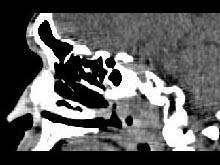

男,52岁,血涕二月余,CT如图所示,最可能的诊断为()A.鼻咽癌B.咽旁混合瘤C.咽部神经纤维瘤D.小涎液腺瘤E.咽旁脓肿

问题 男,52岁,血涕二月余,CT如图所示,最可能的诊断为()

选项 A.鼻咽癌 B.咽旁混合瘤 C.咽部神经纤维瘤 D.小涎液腺瘤 E.咽旁脓肿

答案 A